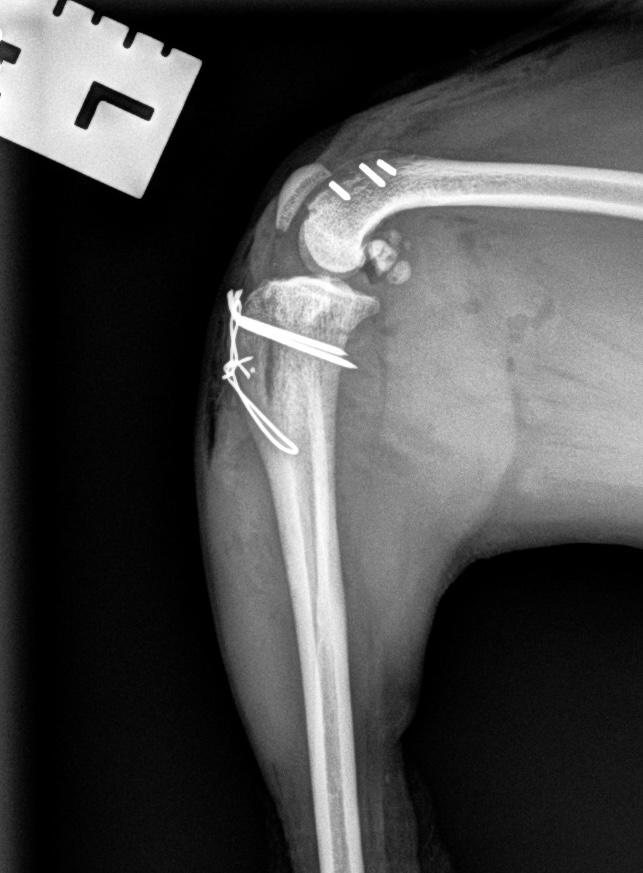

Medial Luxating Patella (MLP) Surgery

A luxating patella occurs when the kneecap moves out of its normal position, which can cause intermittent lameness or long-term joint damage. Surgical correction is available when indicated and is tailored to the severity of the condition and your pet’s clinical signs.

Medial Patellar Luxation (MPL) Repair

Medial Patellar Luxation (MPL) with Extracapsular Repair